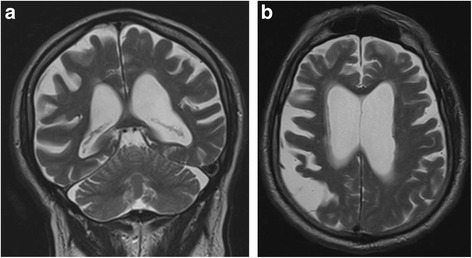

Hersenscan